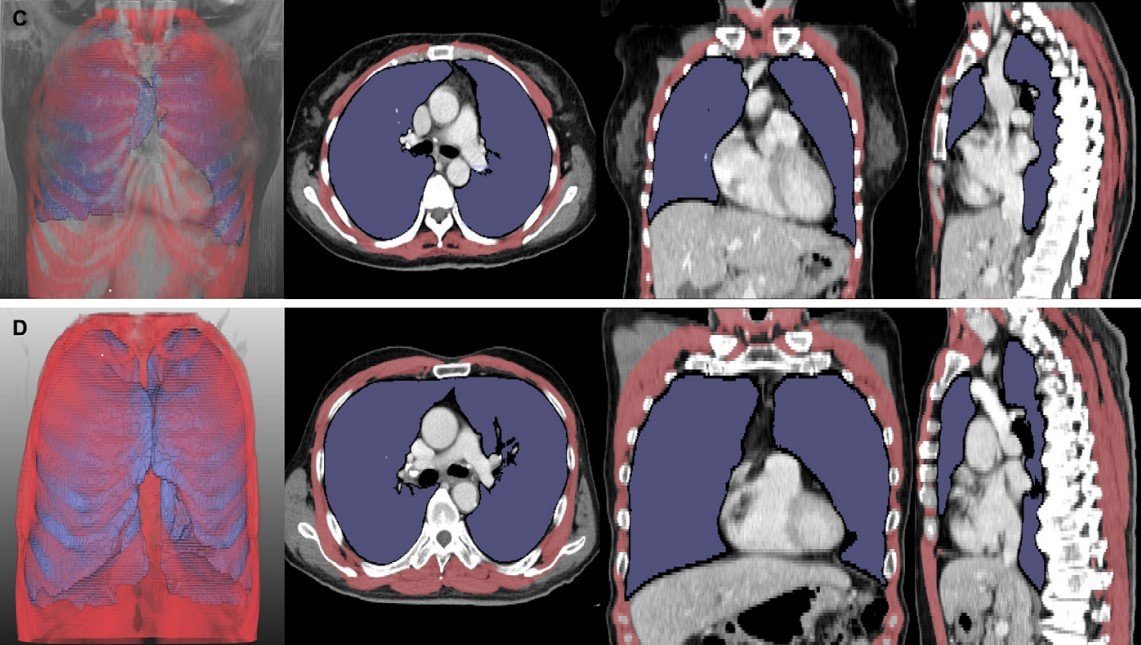

루게릭병 환자의 흉부 CT 분석 결과(서울대병원 제공)

그러나 구강안면 근육이 약해져 구음장애(말과 발음이 부정확해지는 장애)가 동반된 환자는 이 검사의 정확도가 떨어져, 이를 대체할 새로운 검사 방법이 필요했다. 이에 연구팀은 딥러닝 소프트웨어를 통해 루게릭병 환자의 폐와 호흡근 위축 정도를 나타내는 폐 용적 지수(LVI)와 호흡근 용적 지수(RMI)를 개발하고, 병기 및 생존 기간 간 연관성을 확인했다.

그 결과, 폐·호흡근 용적 지수는 병기(1~4기)가 증가할수록 유의미하게 감소했다. 또한, 이 지수들이 낮은 그룹은 높은 그룹 대비 폐와 호흡근 위축이 뚜렷한 것으로 나타나, 기관절개술 또는 사망에 이르는 시점이 빨랐다. 기관절개술은 호흡근육이 약해진 루게릭병 환자 목 부위를 절개해 인공 기도관을 삽입하는 수술이다.

또한 통계 분석에 따르면 폐·호흡근 용적 지수는 기존 폐활량 검사와 유사한 정확도로 환자의 예후를 평가할 수 있었다. 이 결과는 구음장애 환자만 분석한 경우에도 동일하게 나타나, 연구팀이 개발한 영상 기반 지표가 호흡 기능을 평가하기 어려운 루게릭병 환자에서도 폐활량 검사를 대체할 수 있는 가능성을 보여줬다.